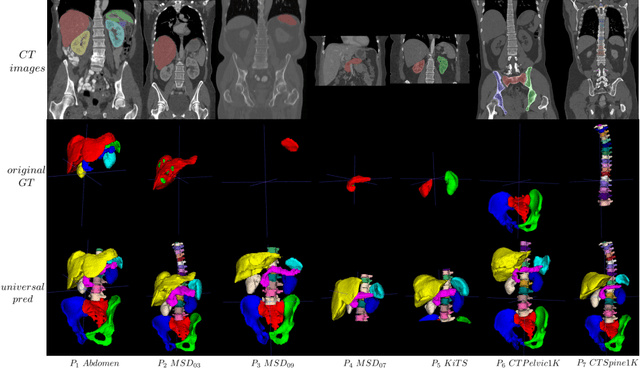

Abstract:In the paper, we present an approach for learning a single model that universally segments 33 anatomical structures, including vertebrae, pelvic bones, and abdominal organs. Our model building has to address the following challenges. Firstly, while it is ideal to learn such a model from a large-scale, fully-annotated dataset, it is practically hard to curate such a dataset. Thus, we resort to learn from a union of multiple datasets, with each dataset containing the images that are partially labeled. Secondly, along the line of partial labelling, we contribute an open-source, large-scale vertebra segmentation dataset for the benefit of spine analysis community, CTSpine1K, boasting over 1,000 3D volumes and over 11K annotated vertebrae. Thirdly, in a 3D medical image segmentation task, due to the limitation of GPU memory, we always train a model using cropped patches as inputs instead a whole 3D volume, which limits the amount of contextual information to be learned. To this, we propose a cross-patch transformer module to fuse more information in adjacent patches, which enlarges the aggregated receptive field for improved segmentation performance. This is especially important for segmenting, say, the elongated spine. Based on 7 partially labeled datasets that collectively contain about 2,800 3D volumes, we successfully learn such a universal model. Finally, we evaluate the universal model on multiple open-source datasets, proving that our model has a good generalization performance and can potentially serve as a solid foundation for downstream tasks.